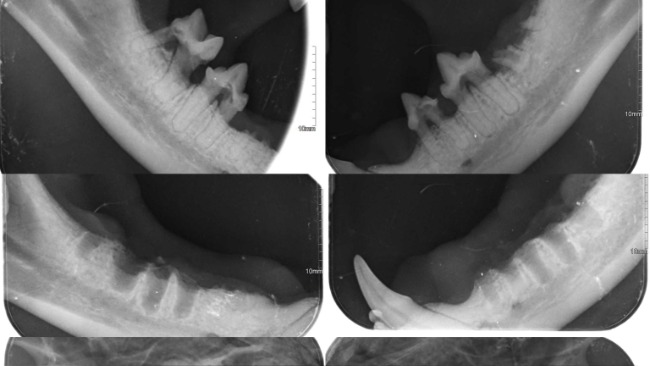

Od kwietnia-maja tego roku P. Hanna zauważyła że przychodzący do niej kot ma słabszy apetyt, nieprzyjemny zapach z jamy ustnej, matową sierść, często przychodzi zaśliniony i apatyczny. Nie zwlekając Pani zapisała kota na konsultację stomatologiczną. W trakcie badania jamy ustnej zaobserwowano silny stan zapalny dziąseł, obrzęk, krwawienie, a także resorpcję zębów.

11/06-Został przeprowadzony zabieg stomatologiczny, zgodnie z założeniami Łobuz miał usunięte wszystkie zęby policzkowe oraz sieczne. Na RTG uzębienia uwidoczniono spory zanik kości zębodołu oraz liczne zmiany resorpcyjne (FORL). Od wczoraj dzięki Wam Łobuz się może cieszyć życiem bez bólu!!!